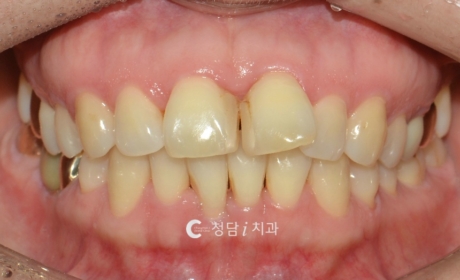

상악만 발치로 오픈바이트, 삐뚤빼뚤한 치열 교정한 사례

오픈바이트와 삐뚤빼뚤한 치열을 동반한 환자로, 웃을 때 앞니가 닿지 않고 상악 치열이 돌출된 상태였습니다. 정밀 진단 후 하악은 유지하고, 공간 확보와 전치부 배열 개선을 위해 상악 소구치만 발치를 진행하였습니다. 치료 후 앞니가 정상적으로 맞물리며 오픈바이트가 개선되었고, 치열도 가지런해져 심미성과 기능이 함께 회복되었습니다.